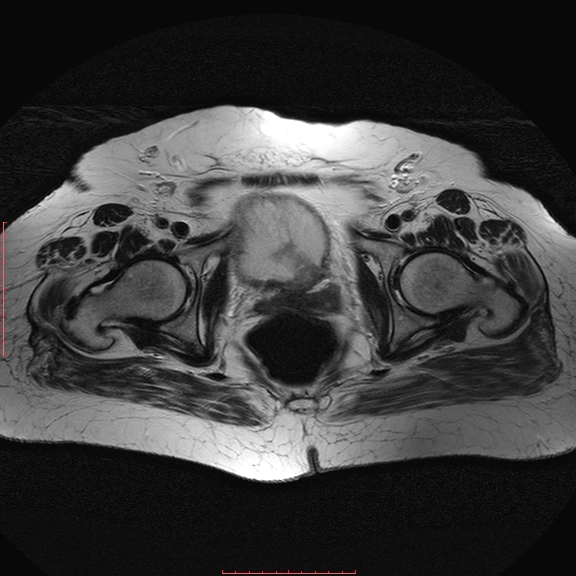

Ung thư niệu đạo nguyên phát (Primary urethral cancer)